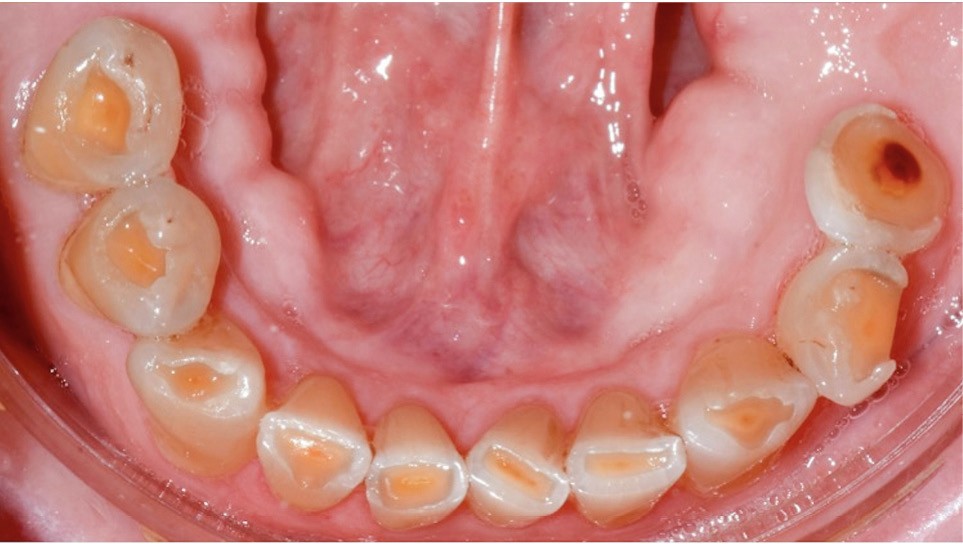

Le cas clinique présenté ici illustre cette démarche thérapeutique. À la suite d’un diagnostic de cancer des voies aérodigestives supérieures, un patient de 68 ans a bénéficié d’un traitement par radiothérapie cervico-faciale, terminée depuis plus de 2 ans. Il souhaite désormais retrouver une réhabilitation fonctionnelle et esthétique de sa cavité orale. Il indique que le délabrement de ses dents antérieures est à l’origine d’un important préjudice esthétique, qui l’a conduit à ne plus sourire. De plus, ses dents absentes réduisent fortement ses capacités masticatoires. Ces différents facteurs influent donc directement son estime de soi et sa qualité de vie, paramètres clés de la rémission dans le cadre oncologique. À l’examen clinique, il présente une perte de calage postérieur, avec des édentements terminaux secteur 2 et 4, ainsi que de volumineuses pertes de substance au niveau des dents présentes (fig. 1).

Bien qu’étant à l’initiative de sa propre prise en charge, le patient reste très anxieux lors de la réalisation des soins, en raison de ses antécédents locaux. Dans ce contexte, une prise en charge thérapeutique conciliant des restaurations partielles collées et des prothèses amovibles à châssis métallique a donc été réalisée, en tâchant d’optimiser la séquence thérapeutique pour limiter le nombre de séances et maintenir la coopération du patient. Nous détaillerons ici les étapes clés de la réalisation des éléments collés.